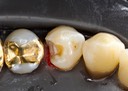

Joe Cha #20 finish